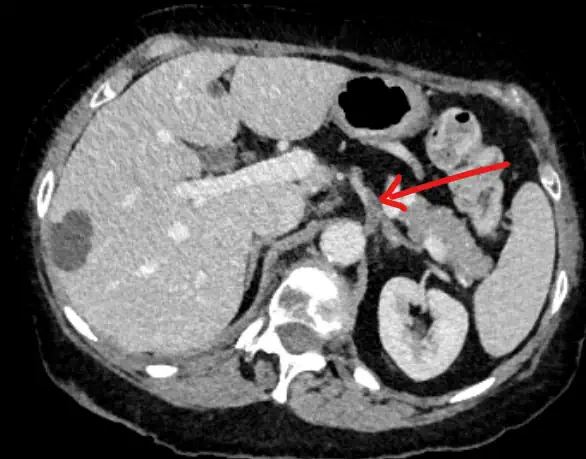

Patients usually present with abdominal pain. But sometimes the finding is incidental. The diagnosis of splenic infarct is usually on axial imaging such as CT.

Once we suspect a splenic infarct, it is important to review the images with radiology. Specifically, splenic lymphoproliferative disease can mimic infarctions. So it is important to confirm the diagnosis.